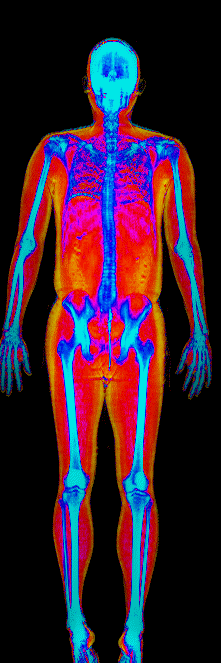

This page features real, anonymized DEXA scan images from BodyStats clients, organized by gender and body fat percentage in 5% increments. DEXA (Dual-Energy X-ray Absorptiometry) is the clinical gold standard for measuring body composition — far more accurate than scales, calipers, or visual estimates.

Each colorized scan shows the distribution of fat tissue (shown in warmer colors) and lean tissue (cooler colors) throughout the body. Compare your own DEXA scan to others in your range, or see what different body fat levels actually look like on a scan.

Male DEXA Scans by Body Fat %

15 to 20% body fat